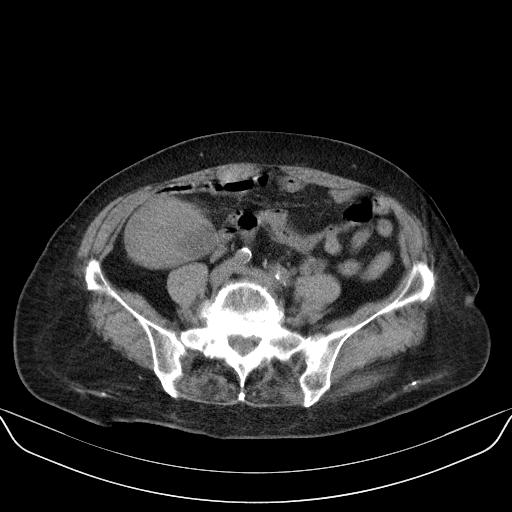

以下是引用yuhongjun在2010-3-12 6:32:00的发言:[br]回肠末端间质瘤,不除外阑尾粘液囊腺瘤,臀部注射性肉芽肿钙化. [br] [br]